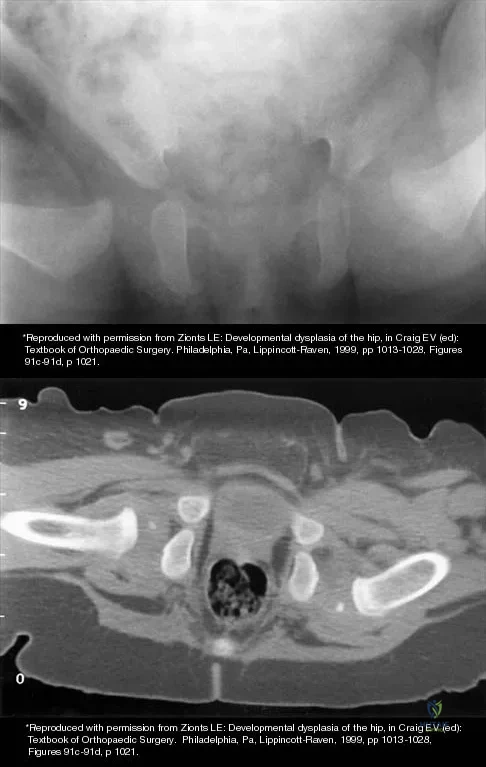

The mother of a 3-month-old infant states that she has difficulty positioning the infant's legs during diaper changes. Examination reveals limited abduction of both hips and a negative Ortolani sign. A radiograph reveals bilaterally dislocated hips. Initial management consists of guided reduction in a Pavlik harness, with weekly follow-up. Figures 57a and 57b show the radiograph and CT scan obtained after 6 weeks in the harness. Management should now consist of

Explanation